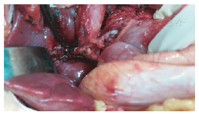

患儿仰卧位,原上腹肋缘下切口;稍微分离切口下粘连;行小肠系膜静脉的二级血管穿刺置管,测压和造影检查,了解门静脉的病变情况;将肝脏的镰状韧带和右侧三角韧带游离;游离肝门的了解原搭桥血管的形态;将胆囊从胆囊床上游离,保留胆囊血管和胆囊壁完好无损;沿着门静脉右支的走行方向劈开Gallison鞘,在其后方找到门静脉的右支,沿着静脉壁向左右游离,至少2 cm长度(图1),必要时沿着门静脉右支的表面将肝裂劈开以延长静脉的游离长度;穿刺门静脉,测压和造影;切开肝十二指肠韧带外侧壁表面的腹膜,在其内找到梗阻近端粗大门静脉的主干,游离静脉的前壁放置血管侧壁阻断钳。根据测量门静脉主干至肝门静脉右支之间的距离,截取肠系膜下静脉,其直径要在5 mm以上。首先用侧壁钳阻断门静脉右支的前壁,根据搭桥血管的直径纵行切开静脉壁,将搭桥血管的向心端与门静脉右支端侧吻合;然后将搭桥血管的远心端与门静脉主干的侧壁端侧吻合,吻合均采用7-0 prolene线间断缝合(图2)。吻合后做门静脉的测压和造影,术中超声了解搭桥血管的通畅情况。